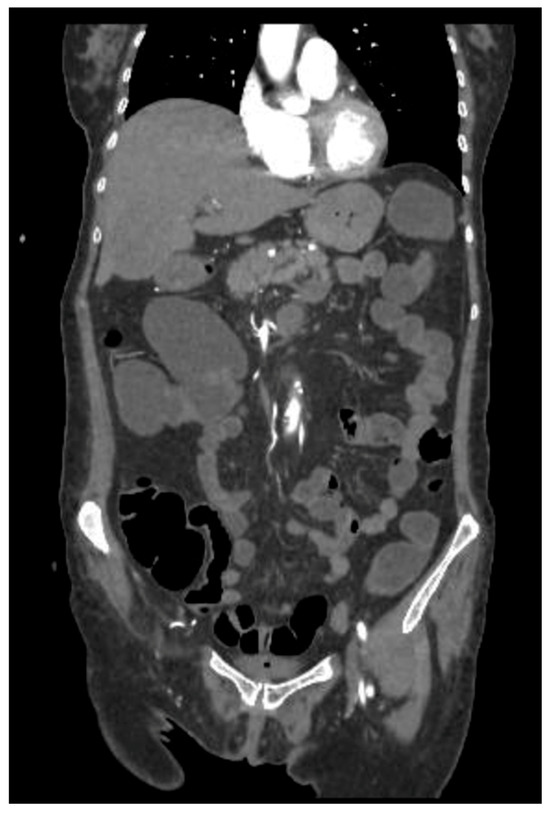

As shown in Figure 3, pembrolizumab may enhance CD8+ T-cell activation and IL-2 release, triggering complement activation and ocular inflammation in genetically predisposed individuals.

Figure 3. Mechanisms of immune-related ocular toxicity induced by pembrolizumab. Anti-PD-1 therapy enhances CD8+ T-cell activation and IL-2 production, potentially triggering complement activation and ocular inflammation in genetically predisposed individuals (e.g., HLA-A29, HLA-B27, and HLA-DR4). These immune responses can lead to ocular damage unresponsive to topical antibiotics, requiring systemic corticosteroids such as methylprednisolone or, in severe cases, ocular evisceration. Created with BioRender.com.